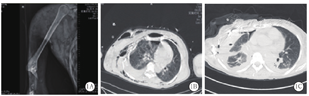

患者女性,44岁,因交通事故伤及头、颈、胸部、右上肢等多处伴意识障碍1 h于2020年4月6日07:00入院。入院查体:体温35.6 ℃,脉搏152次/min,呼吸频率30次/min,血压86/50 mmHg(1 mmHg=0.133 kPa)。患者呈嗜睡状态,右侧眼眶周围及右侧颊部肿胀、青紫,皮肤严重擦伤伴渗血,结合膜苍白,口唇轻度发绀,右侧胸廓塌陷畸形,伴有反常呼吸,胸壁皮肤大片青紫伴广泛皮下握雪感;右肺呼吸音低,可闻及干湿啰音;心率150次/min,律齐,各瓣膜听诊区未闻及病理性杂音;腹软,无明显压痛及反跳痛,肝脾肋下未触及,移动性浊音阴性;右上肢"屈曲"畸形伴多处假关节形成,可触及多处骨摩擦感。实验室检查:血常规示白细胞计数(WBC)7.21×109/L,红细胞计数(RBC)1.59×1012/L,血红蛋白(Hb)50 g/L,血小板计数(PLT)60×109/L,血糖14.9 mmol/L;尿常规示葡萄糖+++,尿隐血+++,尿蛋白+++,可见透明及颗粒管型;凝血功能示凝血酶时间(TT)118 s,凝血酶原时间(PT)19 s,国际标准化比值(INR)1.78,活化部分凝血活酶时间(APTT)240 s,纤维蛋白原(Fib)0.1 g/L;血生化示丙氨酸转氨酶(ALT)52.6 U/L,天冬氨酸转氨酶(AST) 81.1 U/L,总蛋白(TP)53 g/L,白蛋白(Alb)35.2 g/L,肌酸激酶(CK)2 565 U/L,肌酸激酶同工酶(CK-MB)131 U/L,乳酸脱氢酶(LDH)5.43 μmol·s-1·L-1,肌红蛋白(Mb)1 600 U/L;吸纯氧条件下动脉血气分析示pH值7.16,动脉血氧分压(PaO2)42 mmHg,动脉血二氧化碳分压(PaCO2)36 mmHg,HCO3- 18 mmol/L,血乳酸(Lac)4.6 mmol/L,氧合指数(PaO2/FiO2)42 mmHg。X线显示右侧肱骨远端及尺桡骨近端粉碎性骨折并右肘关节脱位,周围软组织损伤(图1A)。CT显示右侧眼眶周围软组织肿胀,内壁凹陷性骨折;颈部、胸背部、腹部皮下广泛积气,颈、胸椎多发骨折;右侧肩胛骨粉碎性骨折,双侧肋骨(右侧第1~8肋,左侧第1~2肋)骨折,右侧肺液气胸、挫裂伤,纵隔左偏(图1B)。初步诊断:重度颅脑、颈、胸、右侧上肢多发伤合并休克、重度ARDS、TIC和挤压综合征。

患者入院后立即给予气管插管、右侧胸腔闭式引流、呼吸机辅助呼吸,输注红细胞、血浆、血小板、冷沉淀、白蛋白等损伤控制性液体复苏,维持收缩压在80~90 mmHg,Hb 70~90 g/L。在纠正休克和凝血功能障碍的同时,于当日17:00在全麻下行右上肢软组织清创、截肢术。因右侧胸腔闭式管中引流出大量气体,氧合难以维持,改为双腔气管插管左侧单肺通气。术中发现患者右上肢肩关节下5 cm肱动脉残端搏动,皮肤、肌肉、血管、神经及骨骼广泛损伤,部分失去正常形态结构、失活,遂行肱骨下5 cm线锯离断截肢及坏死组织清创术,40 min后手术顺利结束。术后患者气管导管内出现大量粉红色分泌物,吸纯氧条件下脉搏血氧饱和度(SpO2)0.70,PaO2/FiO2 39 mmHg,在常规处理无效情况下立即给予俯卧位通气,SpO2升高至0.90,PaO2/FiO2 62 mmHg。4月8日患者循环稳定,Lac 1.2 mmol/L。4月13日13:00在左侧单肺通气下实施右侧肺部手术。术中可见右肺叶萎缩,表面有5处裂口,中间段支气管纵向裂口延长至中叶,仅1/3相连,下叶支气管完全断裂(图2A)。行右侧肺破裂处"8"字缝合、肺中下叶切除术,并用肋骨环保器固定第3~7肋,手术2.5 h顺利结束。术后患者出现肺水肿,脑钠肽(BNP)2 900 ng/L,给予左西孟旦强心,提高胶体、限制晶体及利尿等治疗后病情逐渐好转。为便于吸痰及呼吸道管理,4月14日将双腔气管插管改为单腔气管插管。4月17日在纤维支气管镜引导下行气管切开。4月18日患者呼吸困难缓解,PaO2/FiO2为320 mmHg,胸部CT可见右肺中下叶缺失,右侧膈肌升高,右侧上胸廓塌陷,胸腔积液,残留右肺上叶见条索状、斑片状高密度影(图1C)。4月22日,因胸、肩部等处大面积皮肤坏死(图2B),行胸部扩创切痂、坏死组织清除、创伤敷料覆盖微负压引流术。5月25日择期行"邮票"植皮术,效果满意(图2C)。